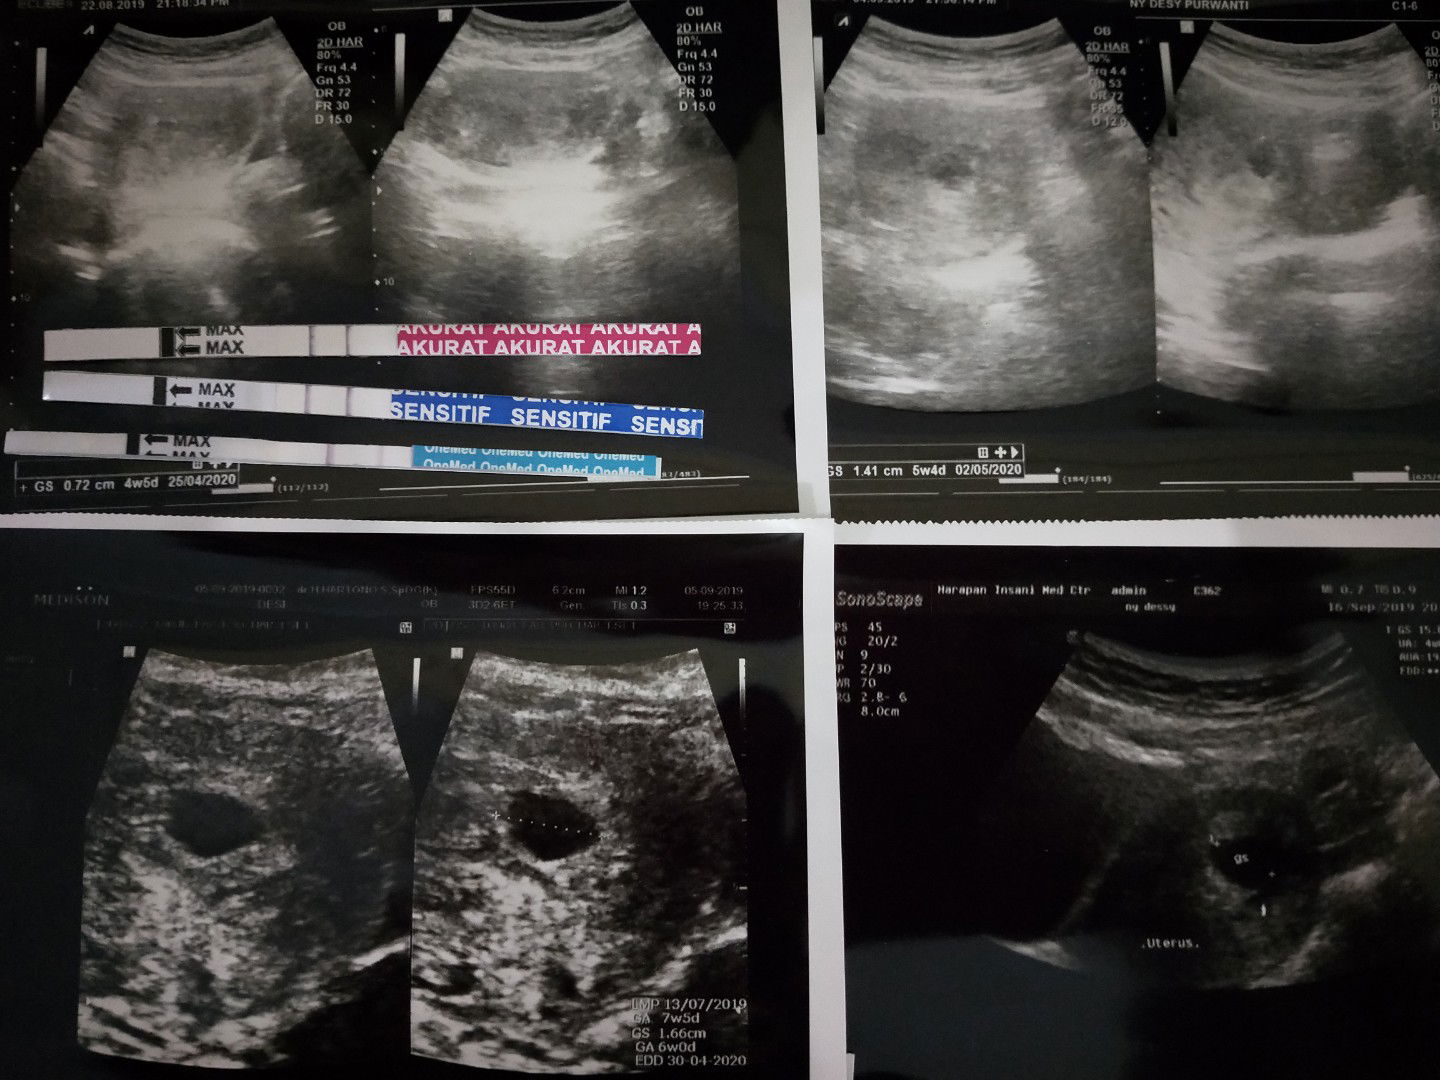

Menanti Kehamilan Anak Ke 2

Hai bunda2, mau tanya adakah disini yg pernah punya riwayat hamil BO trs hamil lagi. september 2019 lalu sata keguguran krna BO dan skrg saya hamil lagi 5 minggu. blm cek ke dokter ntah kenapa saya takut mau ke dokter takut pas di usg ngomong aneh2 lagi. seperti ada trauma. ak pengen tunggu 7 minggu baru ke dokter supaya udh bs liat janin nya. dah skrg saya cm minum nutri mama sm susu hamil. mau tanya buat yg pengalaman BO apakah di kehamilan berikutnya sehat?

Baru 2 minggu yg lalu saya keguguran keluar sendiri tanpa kuret dan tanpa obat peluruh. saya di vonis hamil BO pas umur 6w, udh cek beberapa dokter ada yg saranin lgsg kuret ada yg sarani minum obat buat ngeluarin tp hati ini ga iklas dan berharap msh ada keajaiban tp pas 9w kantong kehamilan keluar sendiri. setelah 2x USG (waktu kantong baru keluar dan setelah darah bersih) dokter bilang rahim bersih dan bagus malah sdh ada indung telur yg siap untuk di buahi jd kalo mau program lg bisa.? Hati mau segera program tp takut. di kasih vit dr dokter buat suami istri biar bibitnya bagus dan ga BO lagi. berserah kepada Allah semoga di kasih kepercayaan lagi dan dikirimkan bayi yg lucu dan sehat. untuk anakku tercinta dirimu selalu ada di hati bunda, msh terngiang betapa bahagianya saat pertama kali menemukan 2 garis di tespek setelah menanti 7thn, msh terasa bahagianya saat dokter bilang positif hamil, walaupun cm hadir sesaat tp kau tetap akan menjadi kenangan paling indah. kita blm berjodoh.